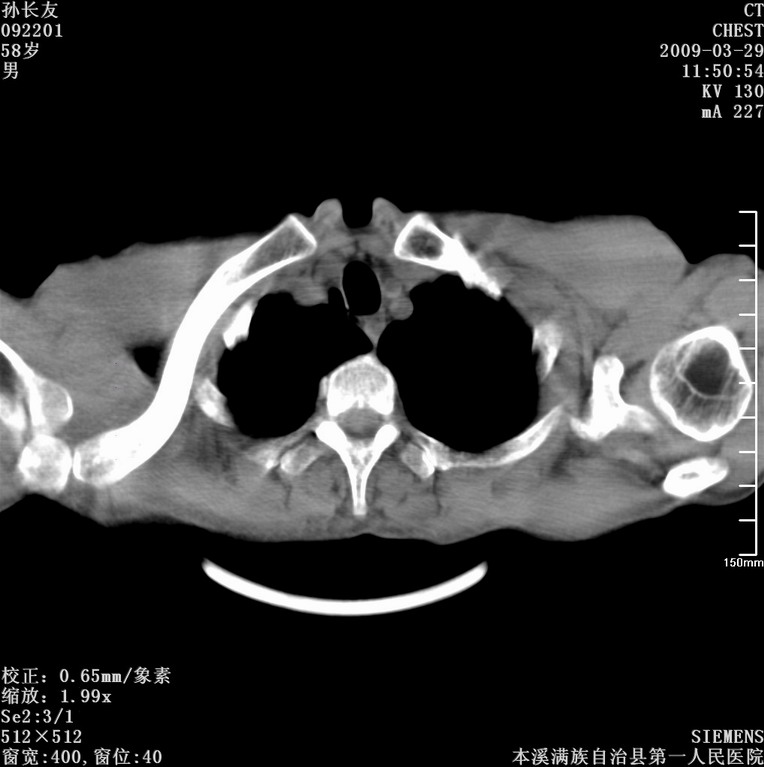

以下是引用liaoqiang在2009-3-30 8:29:00的发言:[br]所上传的层面示气管未见确切异常。

以下是引用bmw011在2009-3-30 12:09:00的发言:[br]所上传的层面示气管未见确切异常。